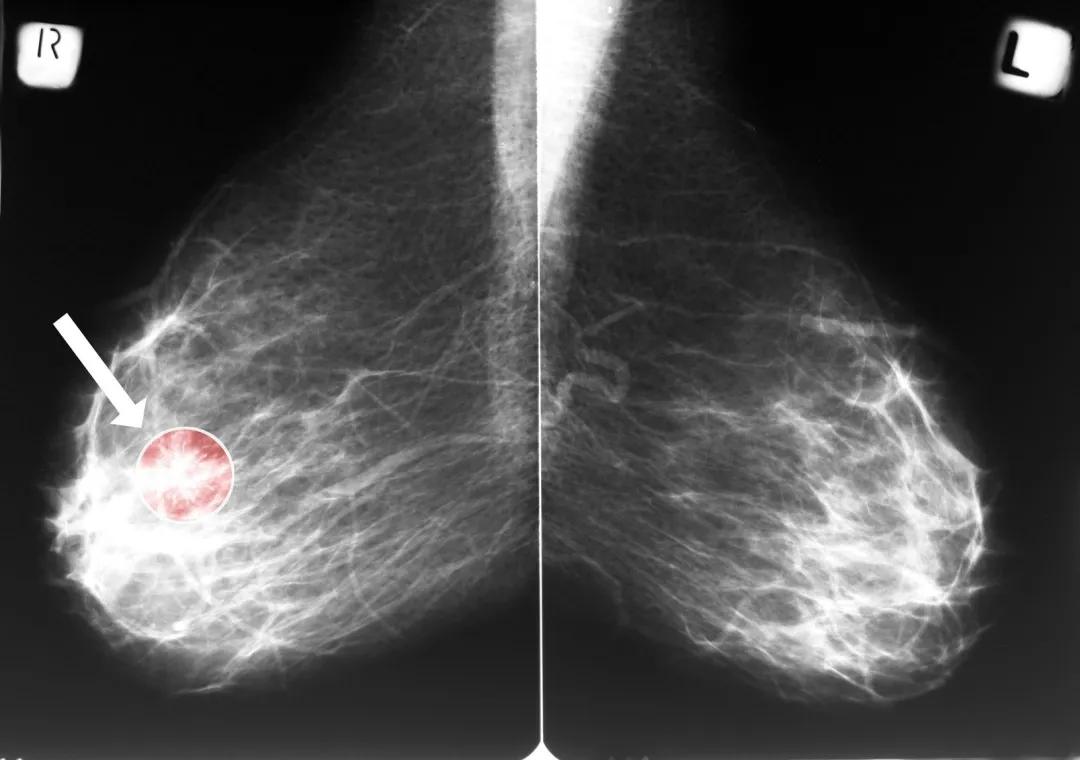

随着高频彩超、X光乳腺照片、MRI等影像学检查手段的发展,临床上常常发现各种大小的肿块,有时甚至小到2-3mm都能检出,那么问题来了,这么小的肿块该怎么办呢?

密切的影像学监测:可以做超声或者X光,检测乳腺肿块病变的大小和变化情况;

40~45岁:适合机会性筛查,每年1次乳腺X线检查,对致密型乳腺(腺体为c型或d型)推荐与B超检查联合。

45~69岁:适合机会性筛查和人群普查,每1~2年1次乳腺X线检查,对致密型乳腺推荐与B超检查联合。

70岁或以上:适合机会性筛查,每2年1次乳腺X线检查。